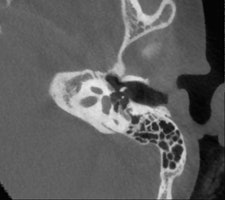

"If the problem is related to conductive hearing loss, then it is most likely to be in the middle ear, in the ossicles, and this requires a CT scan or a conebeam CT. But if the hearing loss is sensorineural, you need to use MRI," stated De Foer, adding that the clinical history of the patient and the clinical examination also will help in choosing the appropriate imaging technique.

He is an advocate of conebeam CT, which is growing in popularity, and recounted the advantages of conebeam CT over conventional CT. He said that he previously conducted all temporal bone imaging on a multidetector-row CT, but he now uses conebeam CT far more frequently. It is different because he uses a flat-panel detector, which provides a high resolution, he explained. Images scan at 0.1-mm resolution, whereas multidetector-row CT scans at 0.5 mm to 0.6 mm.

Several of De Foer's patients were initially scanned on multidetector-row CT and returned postsurgery to receive a conebeam CT. The detail on a conebeam CT is much greater, and the dose is also eight to nine times lower with conebeam in our study of it, he said.

"The level of detail of the ossicular chain is better. For example, the footplate detail is clearer," he said. "The facial nerve running through the middle ear has a bony coverage which is hardly visible on multidetector CT but is very visible on a cone-beam; likewise, the bony covering of the superior semicircular canal, which is important in the Tullio phenomenon."

De Foer also described how conebeam CT is particularly suitable for otosclerosis. This pathology relates to a demineralization of the bone in the inner ear, which prevents the stapes from conducting sound. Conebeam CT shows this in more detail than multidetector-row CT, especially in the evaluation of the footplate.